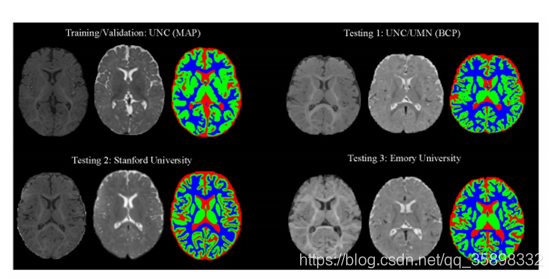

4、iSeg 婴儿白质灰质脑脊液分割

T1/T2两个模态,数据示意图如下:39 patients label情况待定(申到数据)